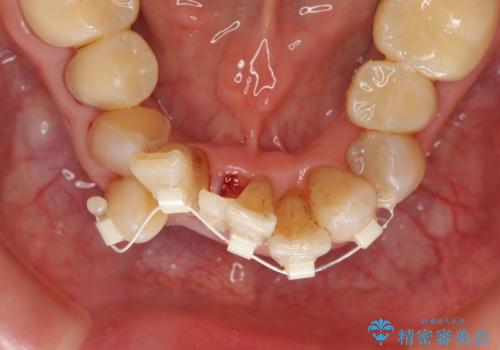

- 上顎前歯の黒ずみの改善、下顎前歯の十度なガタつき、矯正治療とセラミック治療を含む全体的な治療を希望され来院されました。

銀歯を高強度の仮歯に替えたのち、下顎前歯のみの部分矯正→全体的なマウスピース矯正治療(インビザライン)→最終的なセラミック治療と治療を進めます。

矯正治療と目立つ銀歯のやりかえを行ったことでかみあわせだけでなく、審美性・清掃性も改善し口腔内の環境を劇的に改善することができました。